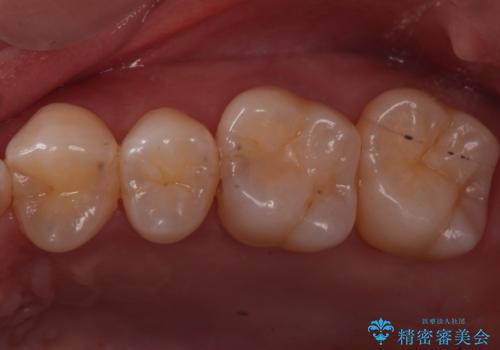

歯と歯の間の虫歯 ゴールドインレーでの修復

- フロスがよく詰まるところがあるとのことで来院されました。

検査の結果、左上の奥歯に虫歯があることが確認されました。

見た目よりも精度を優先したいとのことだったため、ゴールドインレーでの修復処置を行いました。